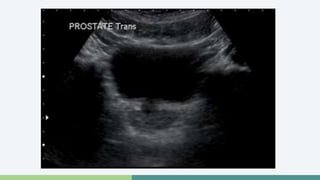

Próstata normal

• Vista transversa

Ultrasonografía • TRUSse realiza después de un DRE anormal o PSA elevado • Biopsias • Lesiones hipoecoicas (60-70%) • Lesiones hiperecoicas (30-40%)

Próstata normal •Vista longitudinal